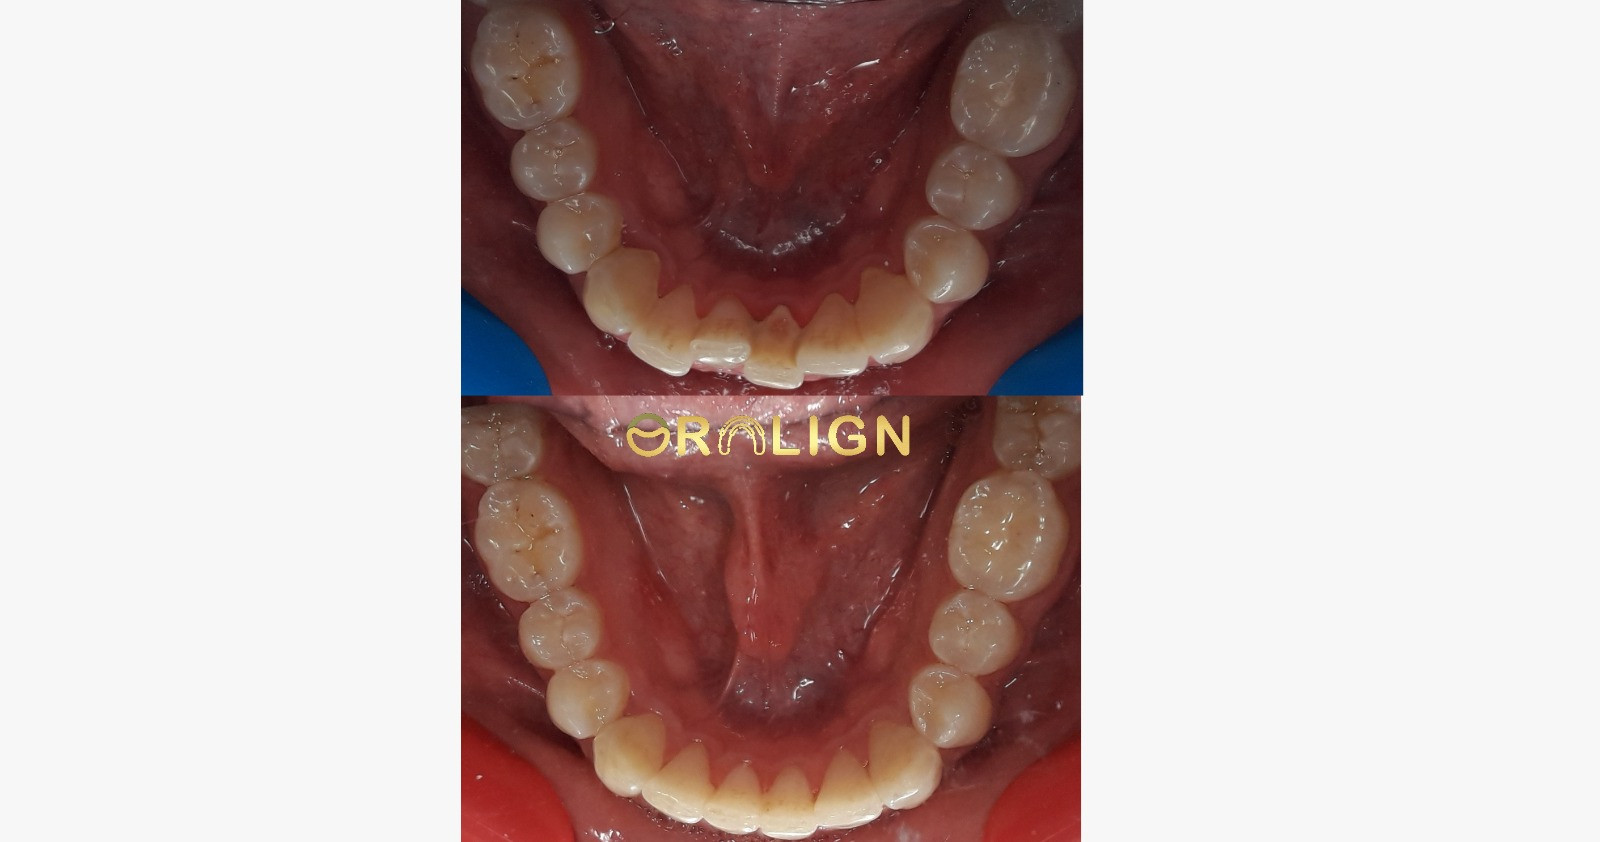

نتائج موثوقة

استعد ثقتك من جديد

شاهد نتائج حقيقية مع آلاف الحالات الناجحة التي حققنا معها المستحيل.